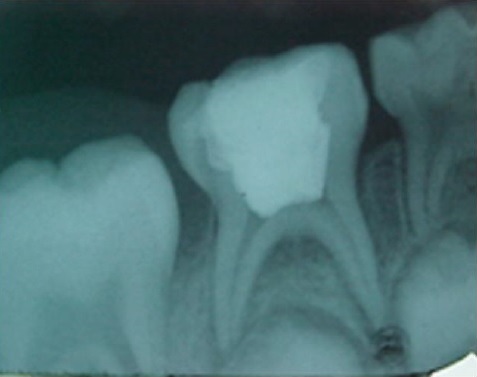

Se evaluaron 20 órganos dentarios con los criterios anteriormente señalados, se les realizó pulpotomía (eliminación de la pulpa de la cámara pulpar preservando la pulpa radicular) de acuerdo con la técnica descrita por la AAOP, exceptuando que previo a la colocación del medicamento o sustancia se tomó una muestra (colocando una punta de papel en la cámara pulpar, dicha punta de papel normalmente se utiliza para secado de conductos en endodoncia) y posteriormente se colocó extracto de orégano a una concentración de 400 mg/ml en una suspensión hidroalcohólica 70:30. La cantidad de líquido colocada fue suficiente para cubrir el piso de la cámara, posteriormente se repitió el proceso de muestra mediante una punta de papel y se llevó a analizar a laboratorio con técnicas de sepsia y antisepsia y para su transporte se empleó el método de Stuart (tubo de ensayo como transporte de tioglicolato). La figura 1 Ilustra el tema del presente trabajo.